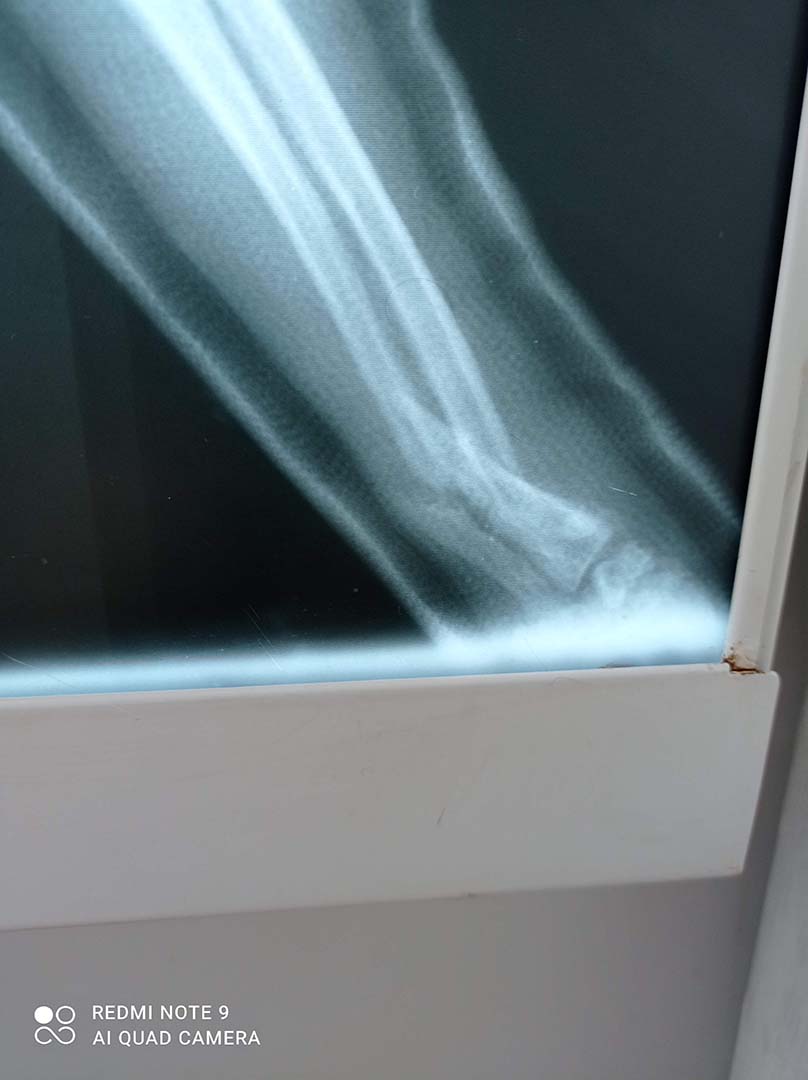

W lecznicy oferowany jest szeroki zakres usług lekarsko-weterynaryjnych a bogate wyposażenie w nowoczesny sprzęt, pozwala na przeprowadzenie na miejscu większości potrzebnych badań, niezbędnych w celu postawienia trafnej diagnozy, co znacznie przyspiesza wprowadzenie właściwego leczenia.